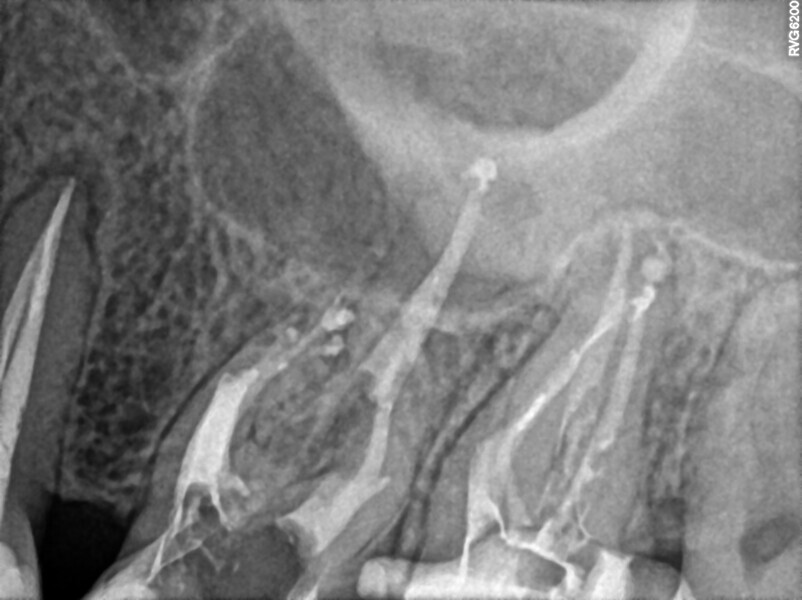

Post-op radiograph of a mandibular molar. (All Images: Bartłomiej Karaś)

A 25-year-old female patient presented to the office owing to constant pain related to the mandibular left first molar. Pulp necrosis was diagnosed. After the emergency appointment, the patient was referred for complete treatment. The tooth was treated in the same manner as described in the previous paragraphs. After creation of the access cavity, the orifices were located. In the root chamber, the orifices of the MB, mesiolingual, DB, distomesial and distolingual canals were present. After pre-flaring and preparation of the middle third, the LPE enhanced irrigation protocol with the SkyPulse laser was performed. After the irrigation protocol in the mesial root, the irrigants started to flow between lingual and buccal canals. Such an observation suggested to the operator that some space in the isthmus had been created. It is worth mentioning that at this stage apical enlargement was not performed. Final preparation of all five canals was performed with the reciprocating file, and the final irrigation protocol was performed as in the previous case. The radiograph clearly revealed that the isthmus space was filled with the sealer. The radiograph and CBCT image revealed that there were four portals of exit in the mesial root.